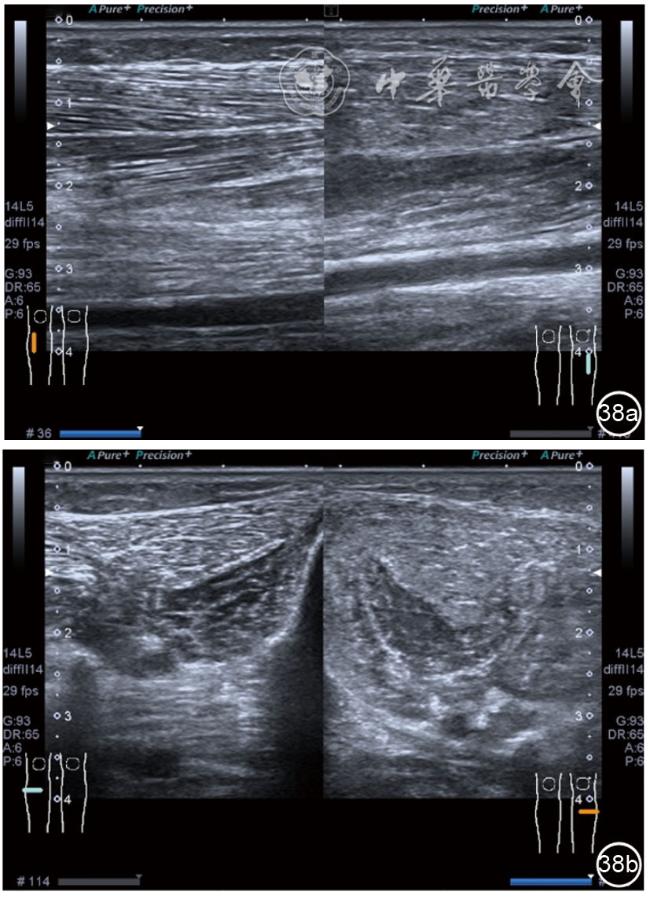

4.腓总神经分支卡压的治疗。常见腓浅神经、腓深神经感觉支卡压。主要表现为足背侧的感觉减退。腓深神经只支配第一、二足趾之间的感觉,腓浅神经支配的感觉区域较多,第一、二足趾之间外的足背感觉均由腓浅神经支配,根据感觉障碍区域确定卡压神经,超声可以明确卡压部位和原因。超声可显示卡压神经增粗,回声减低,局部软组织回声不均匀等(图4445)。治疗以液压松解药物注射为主。以腓深神经为例进行介绍。常见卡压部位在小腿和足背部。根据卡压部位不同,患者采取不同的体位。如果在小腿部采用平卧位,膝关节伸直位即可。穿刺区域常规消毒,探头涂抹耦合剂后套入无菌手套碘伏消毒或使用无菌耦合剂。将探头置于患者皮肤表面,小腿部位采用短轴扫查,确定神经卡压最明显的部位后,用一次性5 ml注射器,应用25G注射针头抽吸0.5%利多卡因4 ml+地塞米松3 mg平面内进针到达神经周围,注意回抽无血液回流后进行注射(图46),完成注射松解,拔出针头,局部压迫3分钟,创可贴覆盖。如果在足背部可以采取平卧位,屈髋、屈膝将足平放于治疗床面。治疗前准备同小腿部,采用长轴显示神经,确定神经卡压最明显的部位后,用一次性5 ml注射器,应用25G注射针头抽吸0.5%利多卡因2 ml+地塞米松1 mg平面内进针到达神经表面进行注射(图47),完成注射松解,拔出针头,局部压迫3分钟,创可贴覆盖。

图47 腓深神经足背处卡压及穿刺注射治疗超声图像